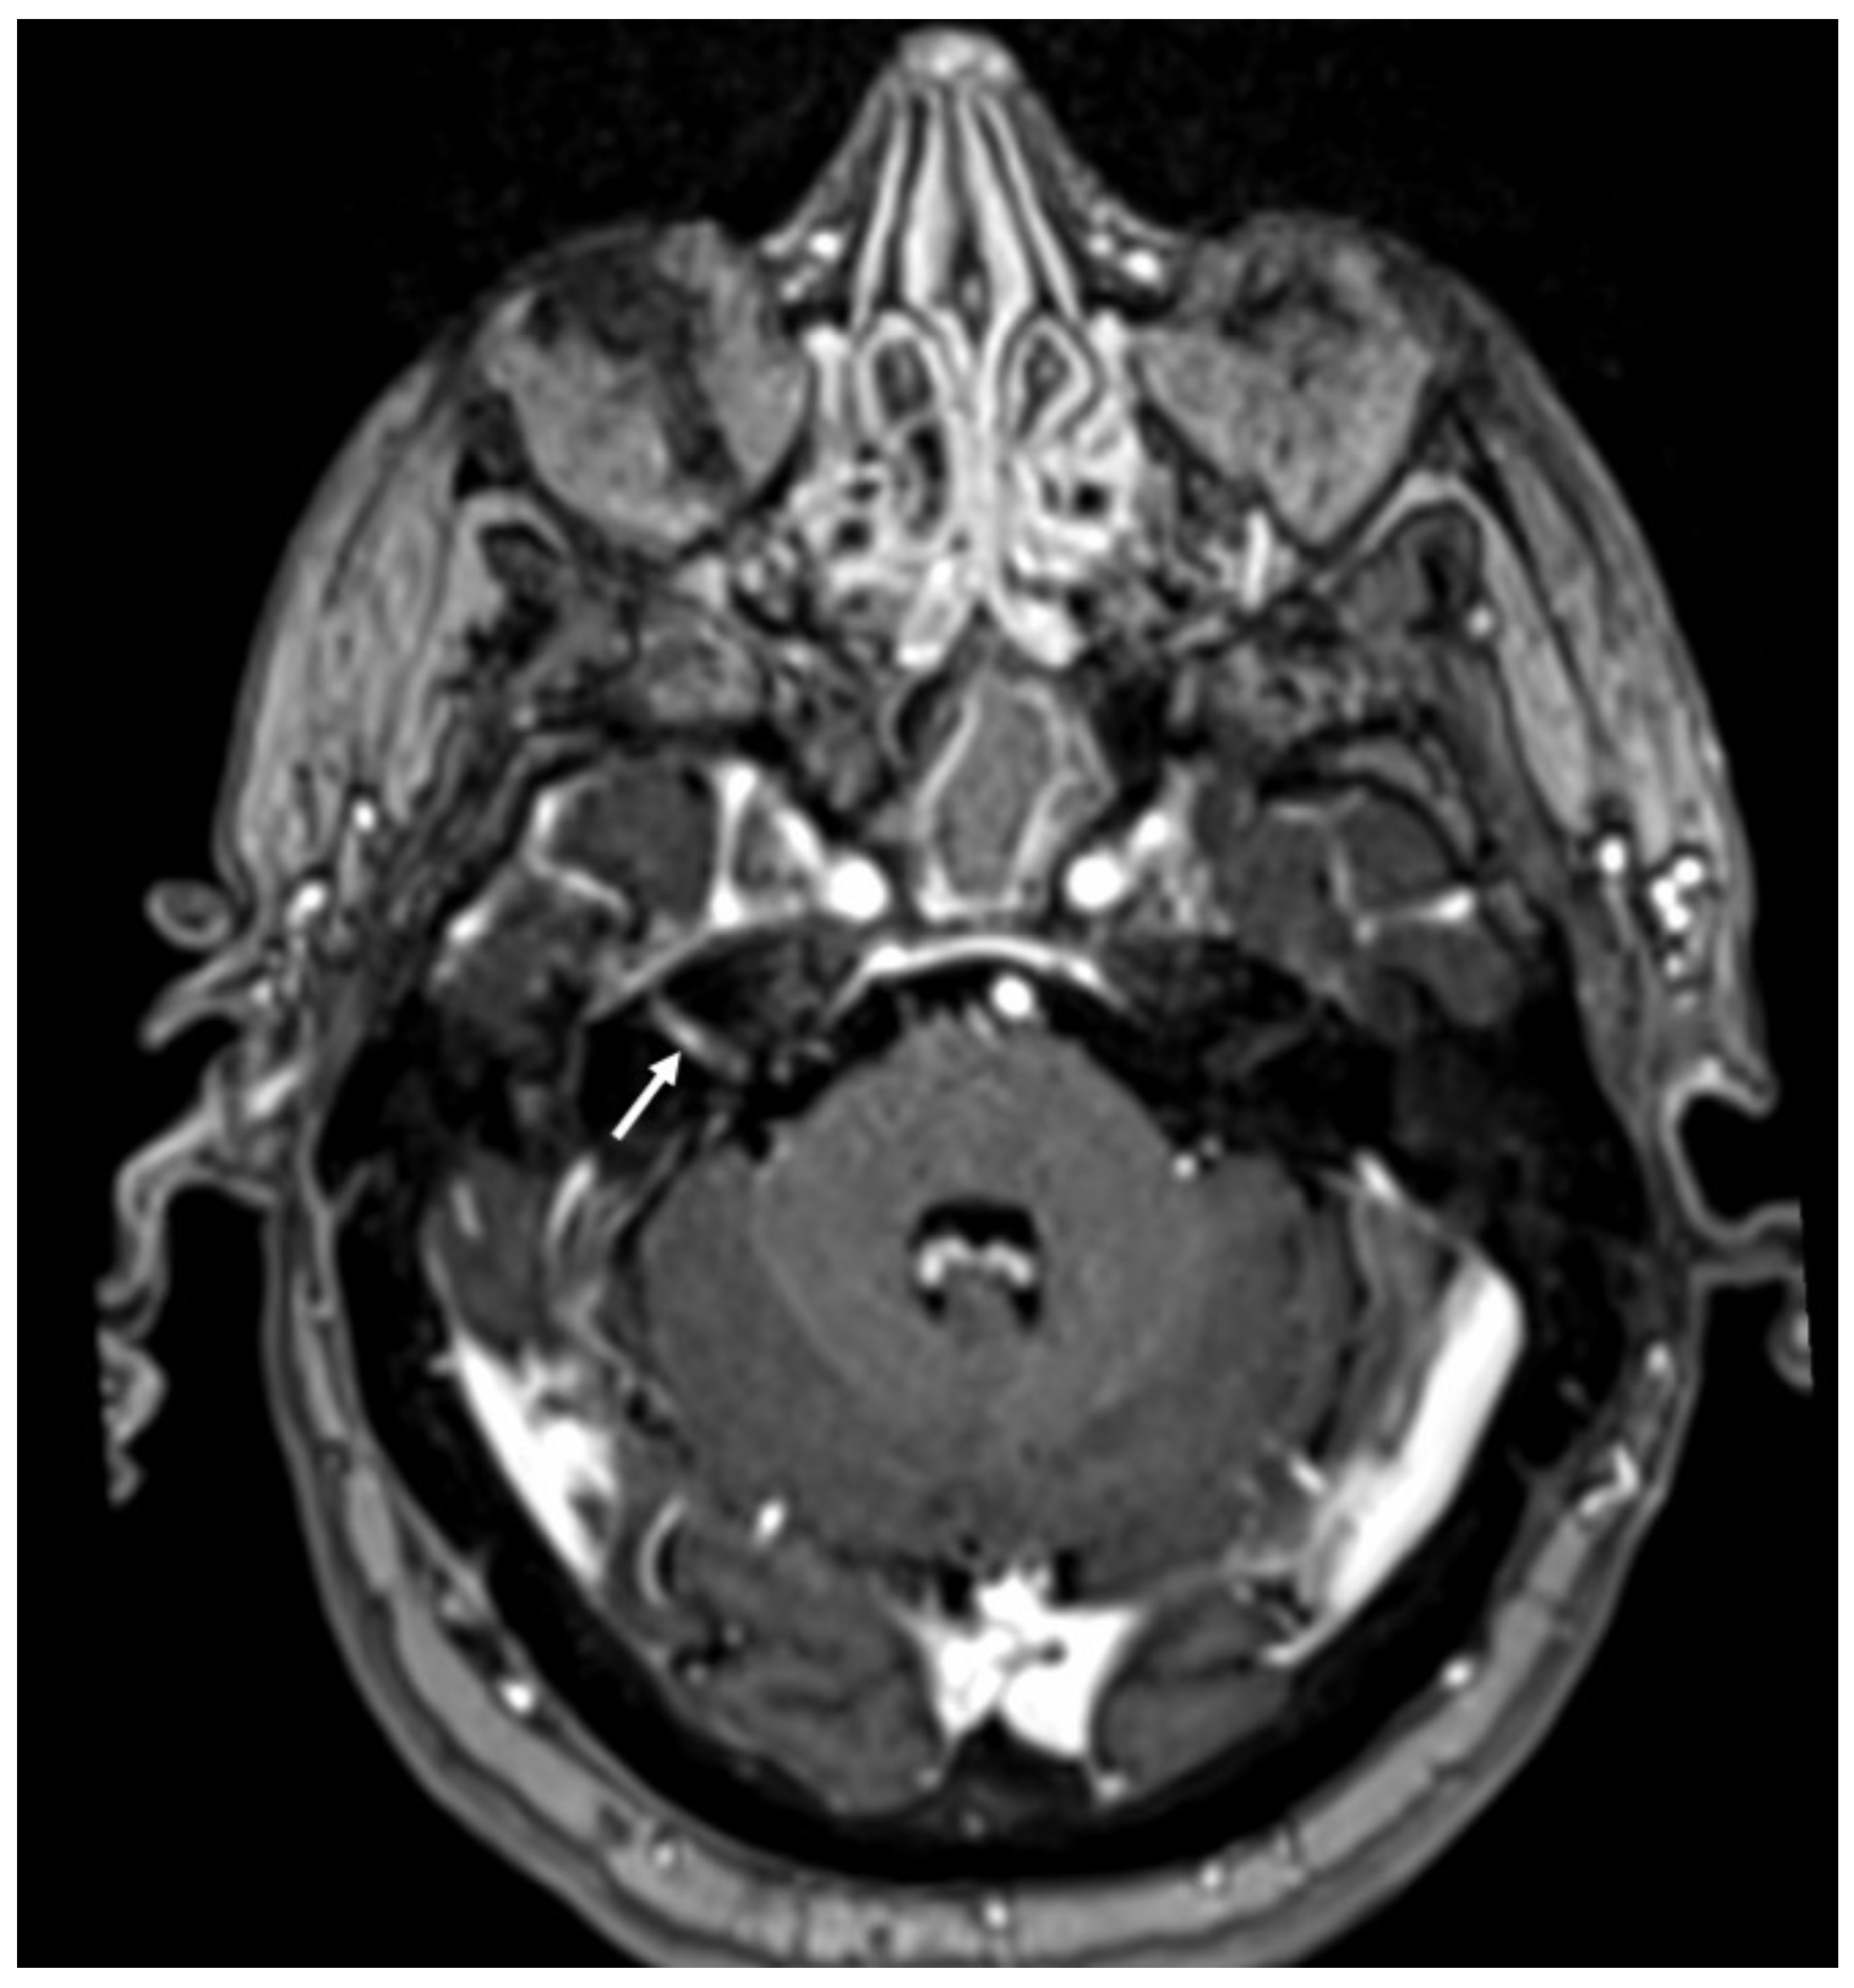

Figure 15.

Enhanced T1 shows enhancement of the right VII-VIII nerves (arrow) in a patient with Herpes virus simplex in the cerebrospinal fluid.